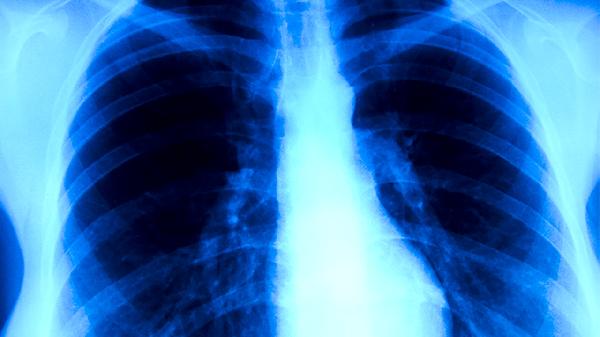

医务人员、矿工等职业人群因频繁接触粉尘或患者,呼吸道黏膜防御功能受损,易通过气溶胶感染。这类患者常出现乏力、食欲减退等全身症状。防护措施包括佩戴N95口罩,定期进行胸部X线筛查,必要时预防性使用异烟肼维生素B6片。